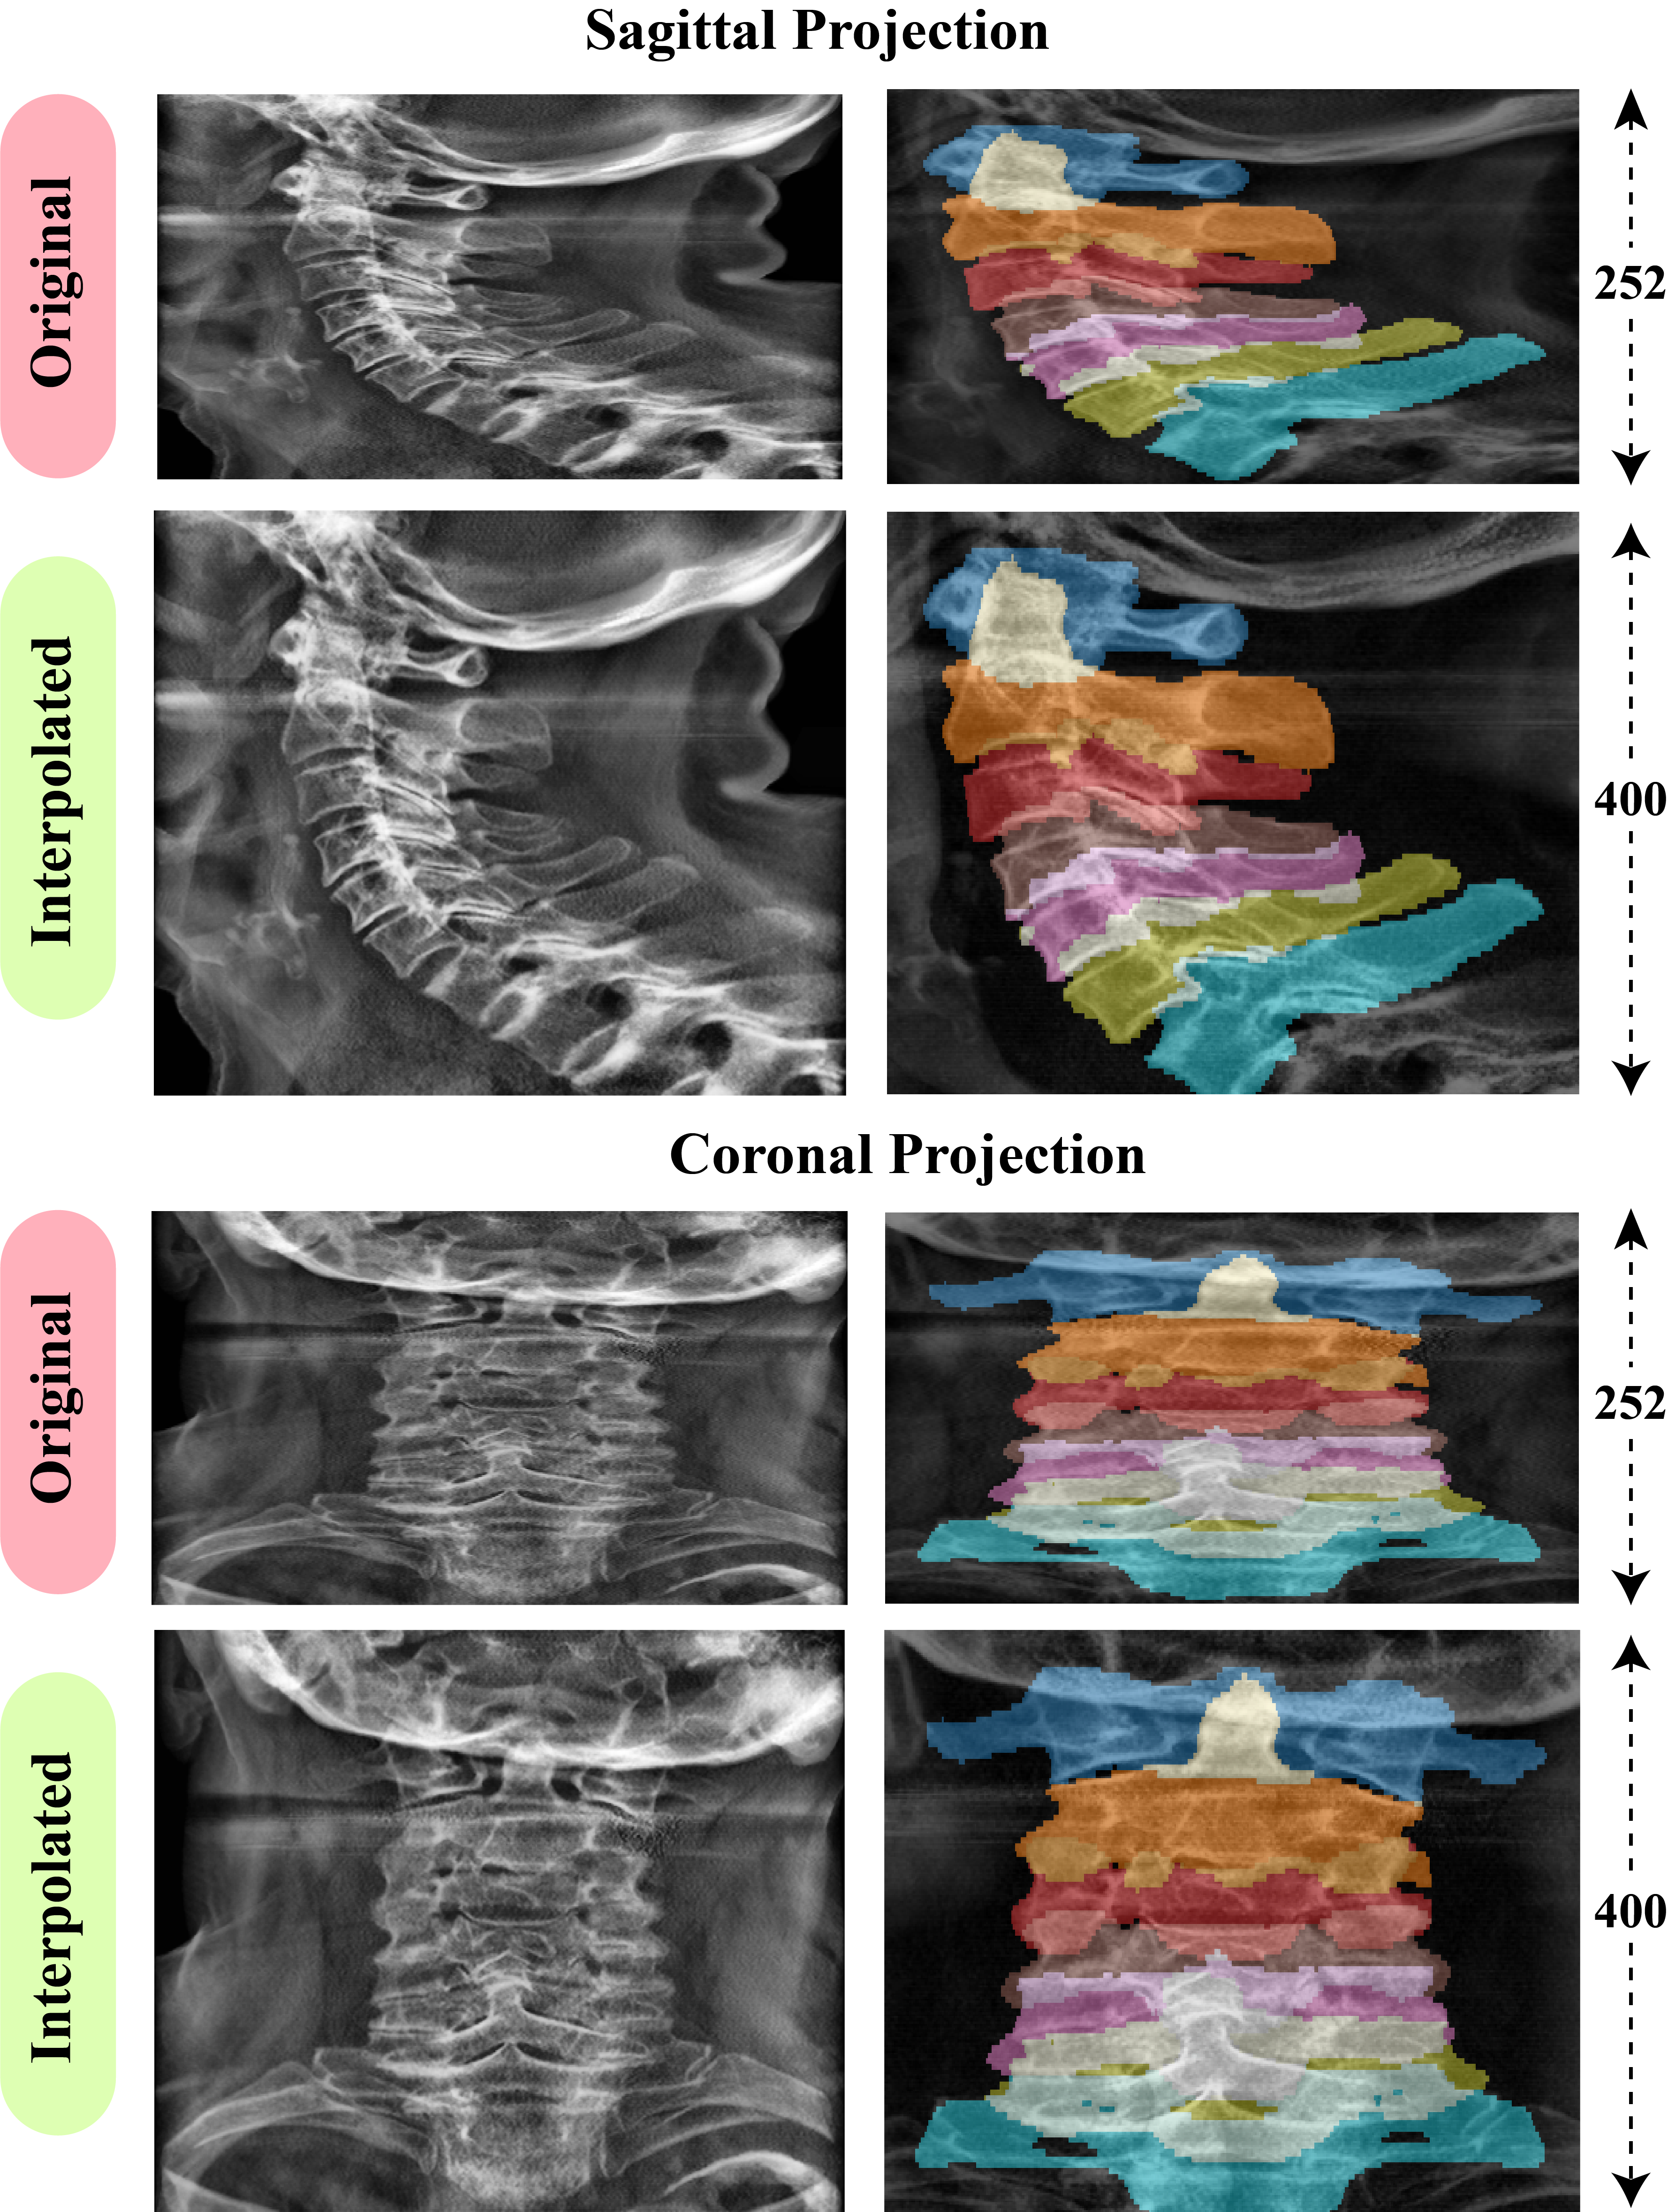

3.4 Cervical Vertebra VOI Segmentation

In this section we discuss in detail our methodology for achieving 3D segmentation from projections for the cervical spine. We utilize the ground truth that was given for 87 patients in the ground truth for training a segmentation model that can effectively segment the C1-C7 vertebrae from coronal and sagittal projections of the cervical spine. Axial projection of the whole volume was not utilized in this step as the vertebra are not separable from a top-down view. Our goal was to approximate the location of the vertebrae, taking segmentations from two perspectives sufficed.

3.4.1 Multi-label Mask Generation

Since vertebra segmentation in this study is performed from coronal and sagittal projection images of the cervical spine VOI, anatomical overlap between neighboring vertebrae is frequently observed in these orthogonal views. Due to cervical curvature and non-linear neck alignment in most patients, distinct vertebral structures may project onto the same spatial location in 2D, causing a single pixel in the projection image to correspond to multiple vertebrae. Further details have been provided in Supplementary Section S4.1.

As a result, conventional multi-class segmentation, which enforces exclusive pixel-to-class assignment, is not suitable for this task. To address this limitation, we adopt a multi-label segmentation strategy, allowing individual pixels in projection space to belong to multiple vertebral classes simultaneously. Multi-label masks are constructed by filtering the cervical vertebrae (C1–C7) from the provided 3D ground-truth segmentation and projecting each vertebra independently along the corresponding viewing axis. The resulting binary masks are then stacked into separate channels to form the final multi-label supervision.

3.4.6 3D Vertebra Mask Estimation and Volume Extraction

Segmentation masks were predicted for coronal and sagittal projections of 2,019 patients. To maintain anatomical fidelity, outputs were reverse-resized and unpadded to original dimensions. We approximated 3D vertebra structure by extruding and intersecting the orthogonal masks. These 3D approximations were used to crop individual vertebrae volumes from all patient volumes. In total, 14,129 vertebrae were extracted; only ~4 were excluded due to noise-induced segmentation failure.

Qualitative examples in Figure 13 illustrate these trends. The proposed DenseNet121 Unet produces more compact and anatomically plausible masks than the comparison models, especially around overlapping vertebral structures. At the same time, all methods struggle to fully capture the spinous processes of the mid cervical vertebrae in the coronal view, consistent with the higher HD95 values reported in Table 5. Given that our downstream task relies on accurate vertebra centered cropping rather than exact subvoxel boundary placement, these residual boundary errors are acceptable, while the observed volumetric consistency across C1–C7 confirms the suitability of DenseNet121_Unet for multi label cervical vertebra segmentation.